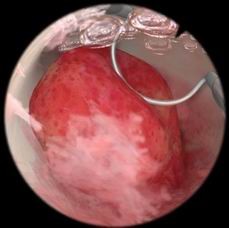

肌瘤切除模块

病例由易到难,简单的病例可发生在子宫底部,复杂的病例可发生在子宫前壁或者靠近输卵管口的地方